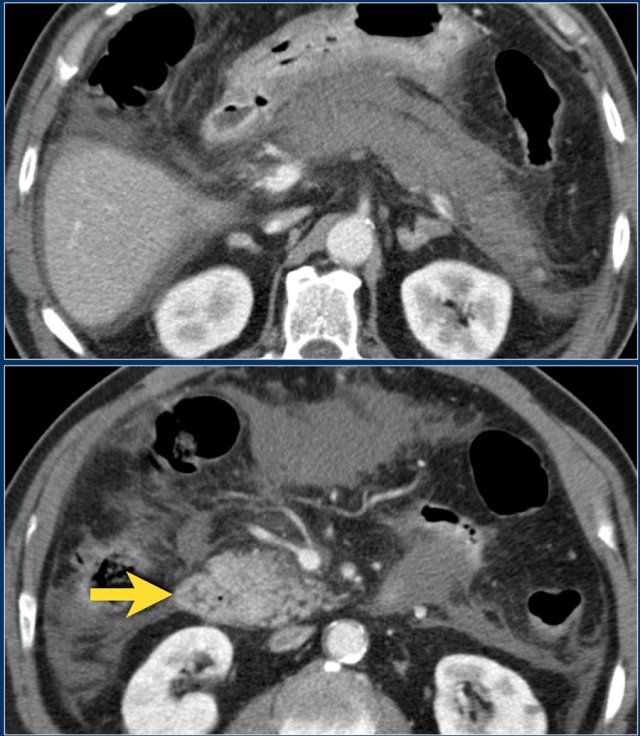

The images are of a patient with acute pancreatitis.

On the upper image is a collection in the area of the pancreatic head in the right anterior pararenal space.

At this stage, it is not possible to distinguish between an acute peripancreatic fluid collection and acute necrotic collection.

On a follow-up scan the collection in the right anterior pararenal space increased in size.

It has fluid density and a thin enhancing wall.

This can be a pseudocyst or walled-off-necrosis and it may or may not be infected.

The patient became septic and a percutaneous drainage was performed.

After drainage the collection barely diminished in size.

The patient underwent surgery and the collection was found to consist of necrotic debris, which was not appreciated on CT, hence this was a walled-off-necrosis and not a pseudocyst.

The necrotic debris was too viscous for successful percutaneous drainage.